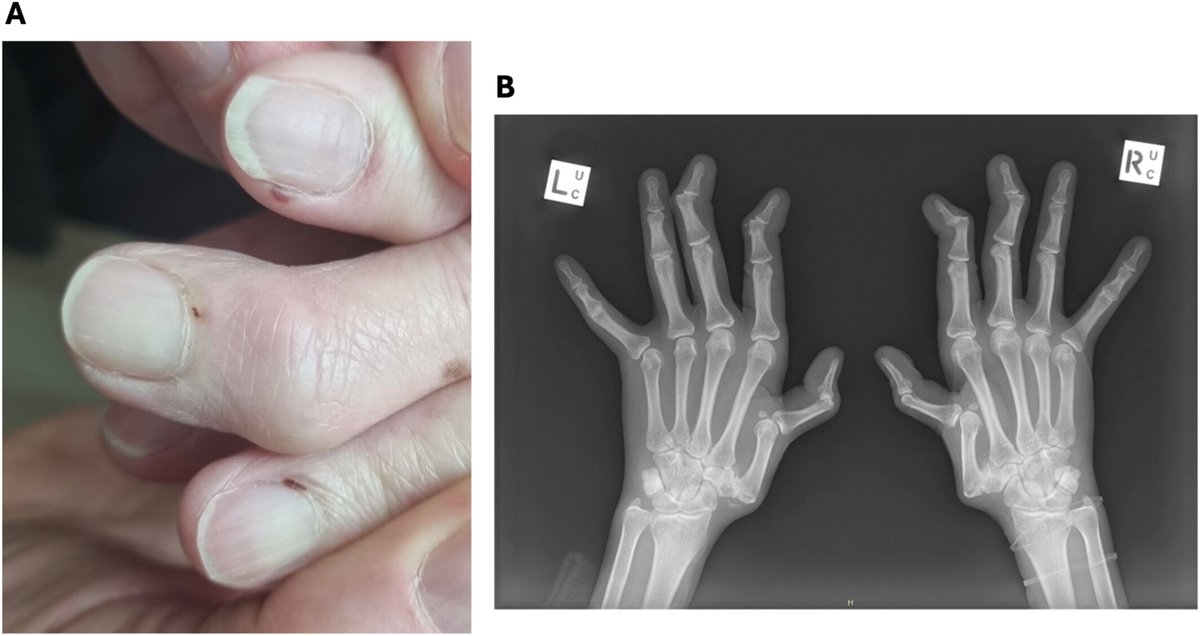

A 60 y/o woman with long-standing SLE treated with prednisone, HCQ, and mycophenolate presented with reddish purple infarctions around the nail folds of multiple fingers (A) that were asymptomatic and resolved after several weeks

Clinical images in ACROR

doi.org/10.1002/acr2.7…